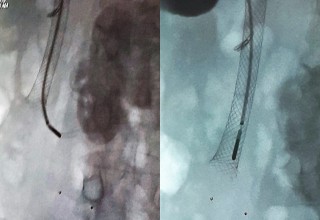

The doctors applied microwave energy to destroy tumor growth prior or post bile-duct stent installation to reestablish and maintain normal bile flow. The microwave energy is applied to the tumors in and around the duct and stent with percutaneous transhepatic cholangiography (PTC) using fluoroscope (real-time x-ray) images of liver, bile-ducts and gallbladder-ducts. A long flexible needle-catheter is inserted into the liver under fluoroscopy to locate and identify blockages using contrast dye. Once the blockage is identified, a smaller diameter catheter with microwave antenna is introduced into first catheter, the antenna is positioned along the duct and the microwave energy is applied using preset temperature and time durations. The antenna is retracted along the duct and the energy application is repeated until the desired length of the duct is treated. The doctors would remove the microwave catheter and verify bile-duct flow with fluoroscopy. The microwave energy application is controlled with direct temperature feedback from the ablation antenna during the procedure to ensure safety and efficacy.

AveCure® microwave ablation system is successfully treating tumors in bile-duct using a minimally invasive technique - the percutaneous transhepatic cholangiography (PTC) incision through the skin to access the tumor through the liver and the patient is left with a small hole in the skin, which quickly heals with almost no scar after the procedure. AveCure® system utilizes a smart antenna in either probe or catheter format and microwave energy controller to select the correct size, temperature and timer settings appropriate for safe, effective and predictable treatment.